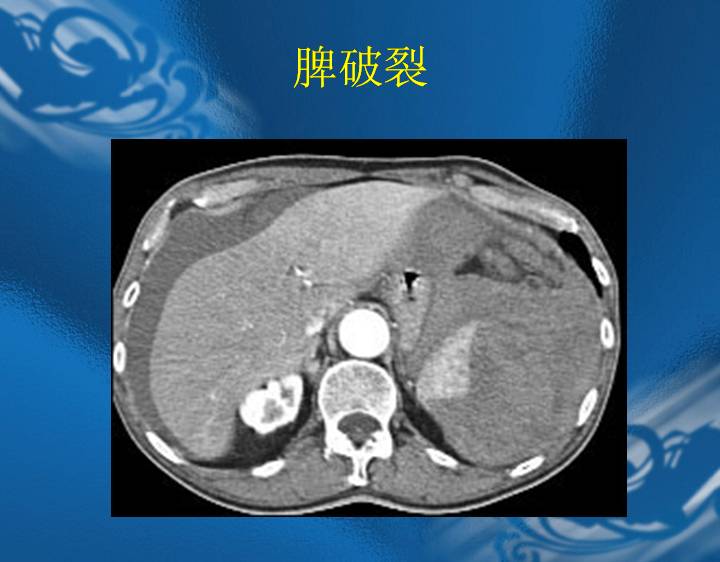

执业医师资格考试“实践技能”影像学辅导资料